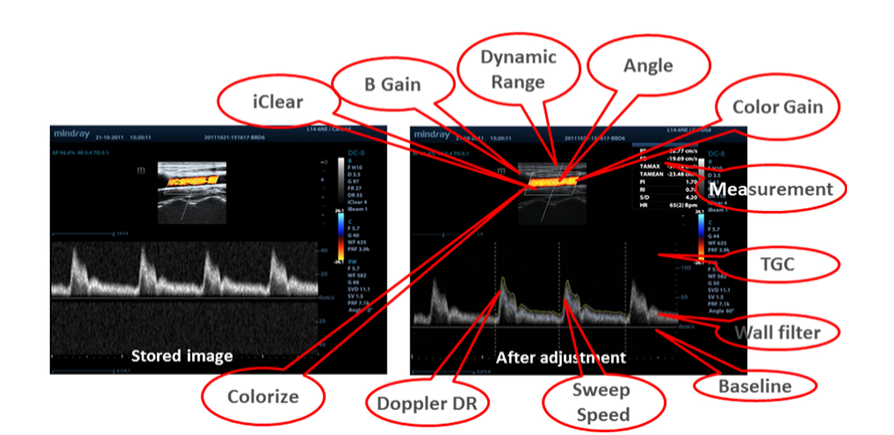

Raw Data

Maximise productivity during scanning with post processing of stored images including parameter adjustments, adding comments and measurements.

iClear

Gain improved image quality based on auto structure detection.

iTouch?

Gain instant auto image optimisation in B, Color and PW Modes with the click of a single key.